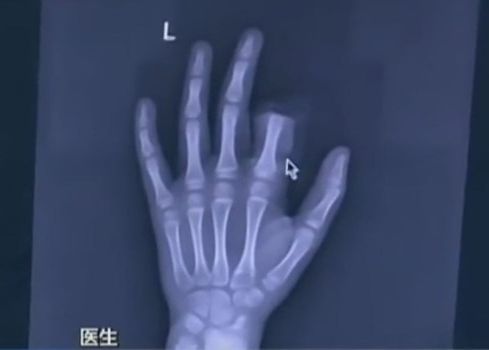

Cele 2 certuri l-au suparat rau pe copil - dupa cel cu tatal sau, s-a ds in bucatarie, a luat un cutit si si-a taiat degetul! Parintii l-au dus de urgenta la spital alaturi de partea sectionata a degetului iar medicii l-au operat timp de 3 ore incercand sa-i reataseze degetul.

Operatia s-a incheiat insa fara succes pentru moment, neputand sa-si foloseasca acel deget. Cu timpul s-ar putea sa redevina functional.